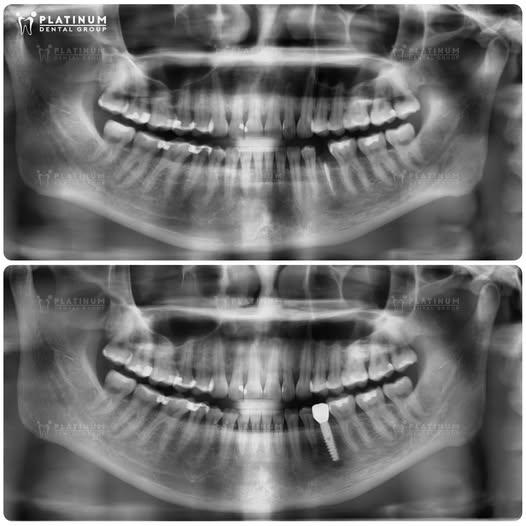

Hình ảnh ca nhổ răng nhiễm trùng và cắm Implant tức thì

Răng nhiễm trùng nghiêm trọng là một trong những nguyên nhân phổ biến khiến nhiều người buộc phải nhổ bỏ răng vĩnh viễn. Không chỉ ảnh hưởng đến thẩm mỹ, tình trạng này còn gây suy giảm chức năng nhai và tiềm ẩn nhiều nguy cơ cho sức khỏe tổng thể. Tuy nhiên, với sự tiến bộ của nha khoa hiện đại, đặc biệt là kỹ thuật cắm Implant tức thì, khách hàng hoàn toàn có thể phục hồi răng mất một cách nhanh chóng và an toàn, thay vì phải chờ đợi nhiều tháng như trước đây.

Tại Platinum Dental Group, quy trình điều trị được cá nhân hóa và thực hiện theo chuẩn y khoa: từ bước chẩn đoán bằng phim CT/X-quang, nhổ răng nhẹ nhàng không đau, đến kiểm soát nhiễm trùng kỹ lưỡng trước khi cắm Implant ngay tại vị trí răng vừa nhổ. Nhờ kỹ thuật tiên tiến, trụ Implant có thể được đặt trong cùng một ngày, rút ngắn thời gian điều trị, giảm xâm lấn và phục hồi thẩm mỹ lẫn chức năng ăn nhai gần như tức thì. Bệnh nhân cũng được theo dõi sát sao hậu phẫu và hướng dẫn chăm sóc đúng cách, đảm bảo kết quả bền vững theo thời gian.